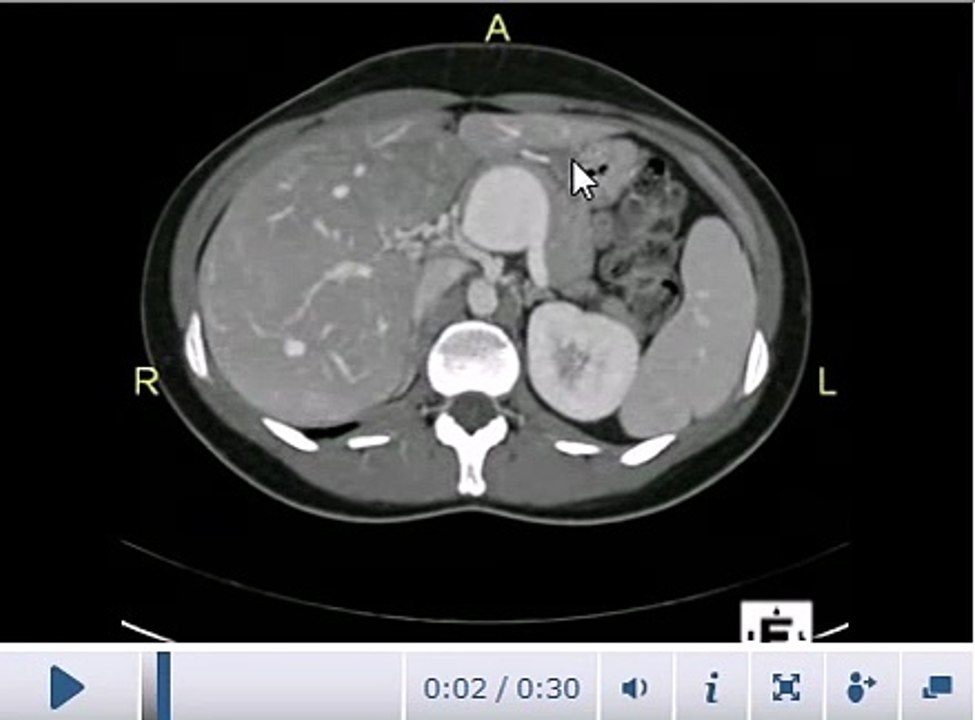

AIMMS LIBRARY CT SCAN COURSE VIDEO NO 11 CT abdomen Anatomy video